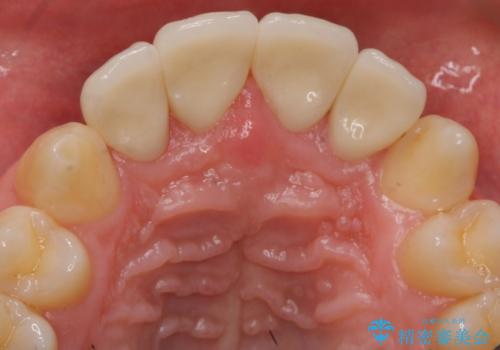

前歯のすき間 セラミックで綺麗に 最短で治療

矯正治療か、セラミックで最短で治すかの選択肢を提示し、セラミックで治すことにしました。

利点は、早く終わる上に、保定の必要がないため負担が少ないことが挙げられます。

全て神経は取らずに、削りました。

長年コンプレックスだったすき間が閉じたとのことで、喜んでいただきました。